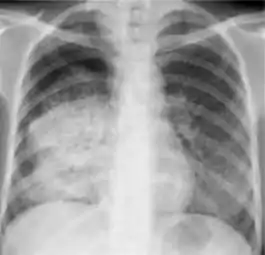

3. Nodule with poorly defined margins - Round density within the lung parenchyma, also called a tuberculoma. Nodules included in this category are those with margins that are indistinct or poorly defined (tree-in-bud sign[3]). The surrounding haziness can be either subtle or readily apparent and suggests coexisting airspace consolidation.

Chest x-ray showing nodule with margins that are indistinct or poorly defined (tree-in-bud sign) in post-primary pulmonary TB.